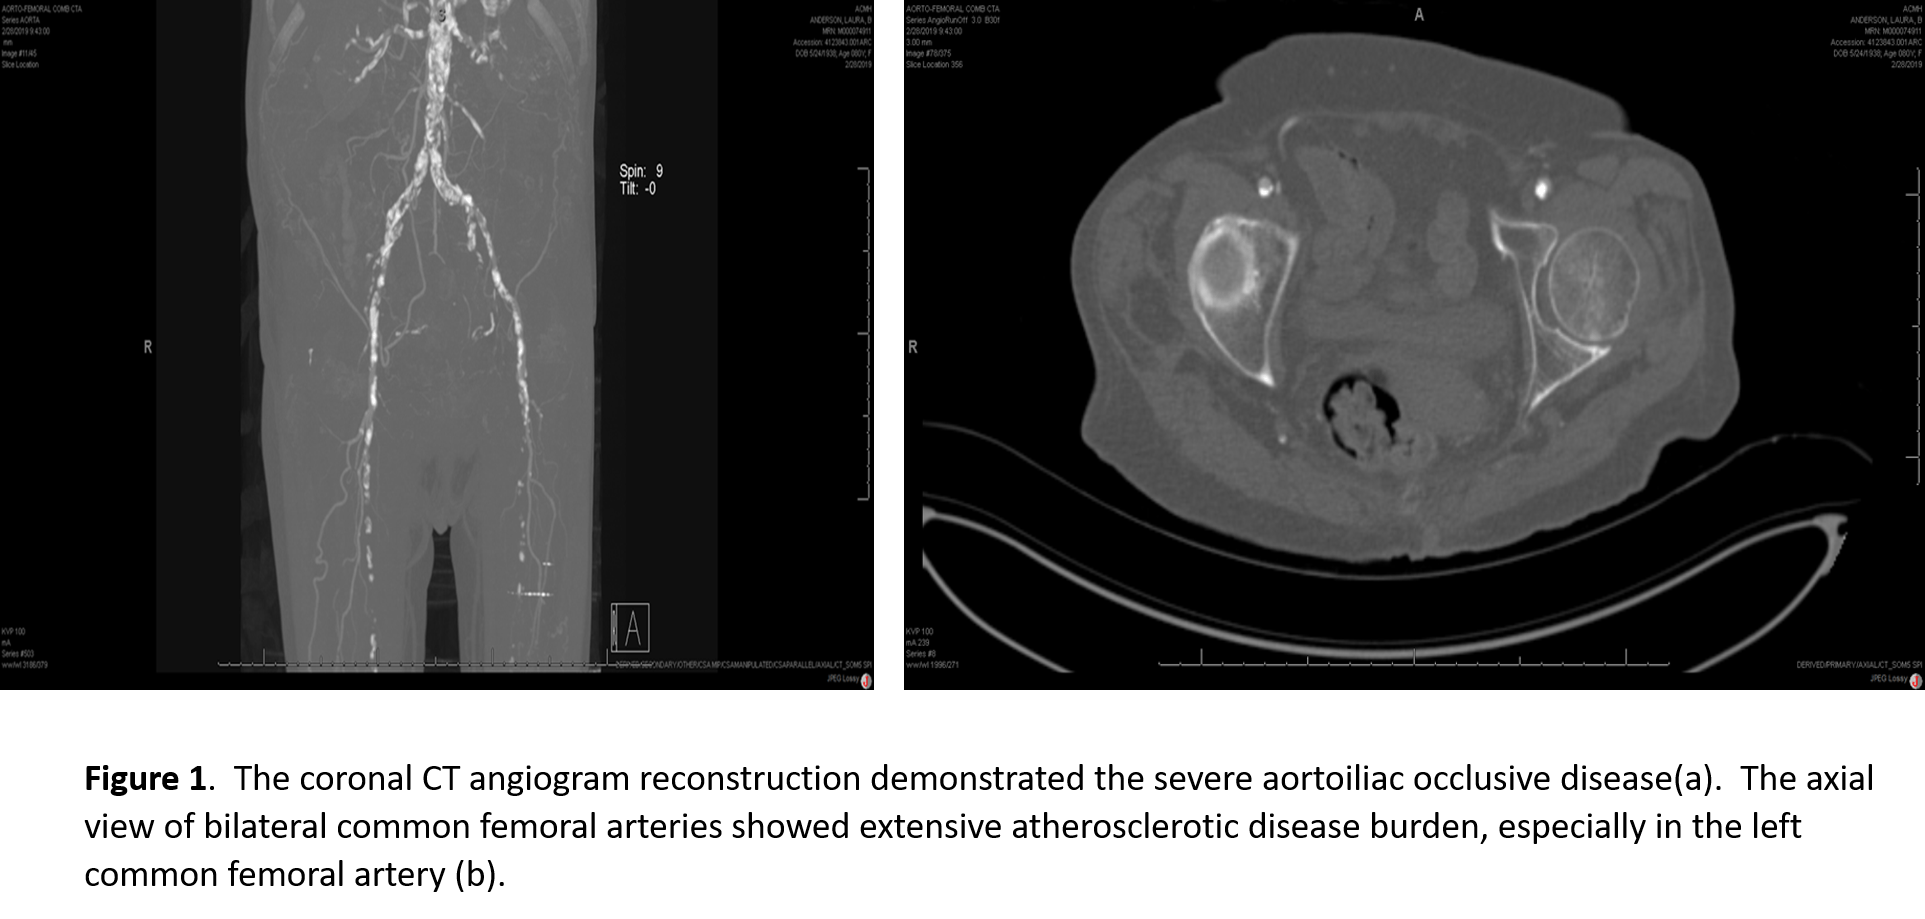

An 80-year-old female was transferred to UPMC Presbyterian from an outside hospital with rest pain, tissue loss, and a mid-aortic and bilateral common iliac artery occlusion (Figure 1a). She had severe three-vessel coronary disease on recent cardiac catheterization. A hybrid procedure was performed via percutaneous, ultrasound-guided access of right common femoral artery and a left femoral exposure to perform an endarterectomy with profundaplasty given its severe atherosclerotic burden (Figure 1b). The chronic thrombotic occlusions of the iliac arteries and aorta were crossed bilaterally, pre-dilated, and stented. Bilateral balloon-expandable stents were deployed simultaneously in the mid-infrarenal aorta in a parallel kissing stent configuration (Figures 2 a-d), and covered self-expanding stents were utilized for the bilateral external iliac disease. She was discharged home with family a few days following the procedure with resolution of her rest pain.